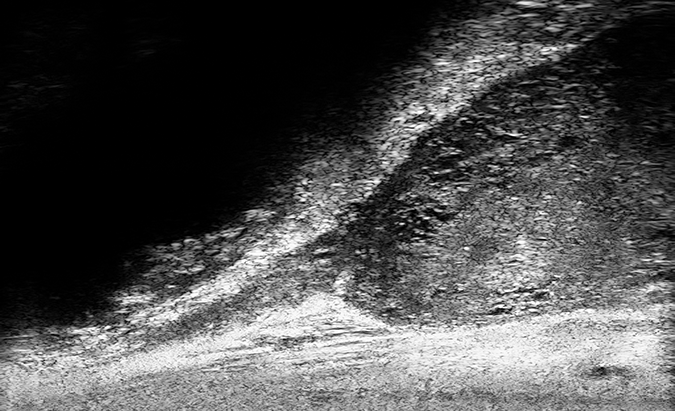

PRI-MUS 4

Heterogeneous “Cauliflower”, “smudgy or mottled” or Bright Echoes (”Starry Sky”)